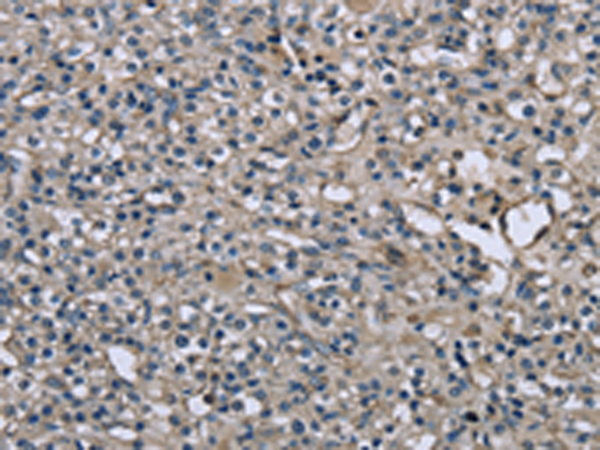

分类: 科研抗体货号: P08308别名: DRR1; TU3A应用: IHC反应种属: Human